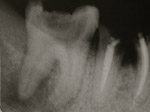

Nécrose infection sur 1ère molaire supérieur. Présence d’une lésion kystique apicale

Désinfection canalaire par traitement endodontique sous microscope.

Cicatrisation osseuse 6 mois post-opératoire.